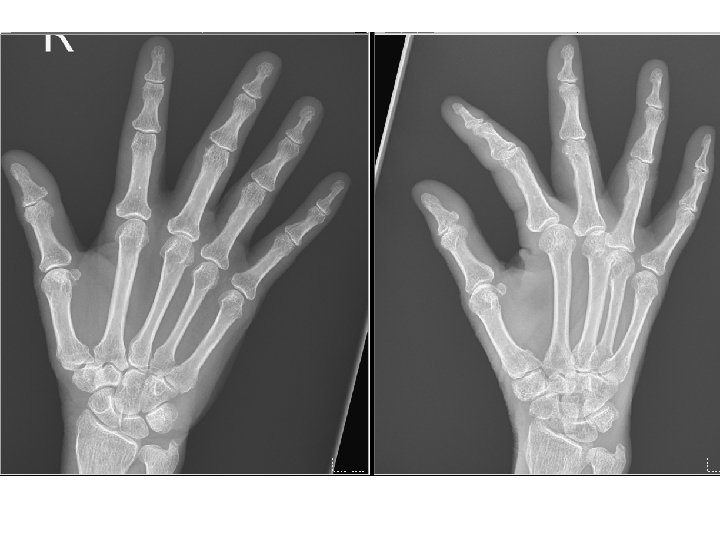

Hospital course (AIR survey) l Immune profile: ANA: 1: 640 H, anti. SSA>240, anti-SSB(-), RF(-), ACPA(-), C 3: 16. 6, C 4: 4. 8, Ig. G: 2010, Ig. A: 480, Ig. M: 43. 4, Ig. E: 14. 1 l HSCRP: 3. 73, ESR: 15 mm/hr

Problem list Chronic lower abdominal pain l Poor appetite + body weight loss l Ascites => Serositis or nephrotic l Polyarthralgia, sicca complex => Suspect Sjogren’s syndrome, D/D: SLE l Others: nausea/vomiting, DOE, microcytic anemia, CBD dilatation l Confirmed: GERD and gastric ulcer, C. difficile associated diarrhea, nephrolithiasis l